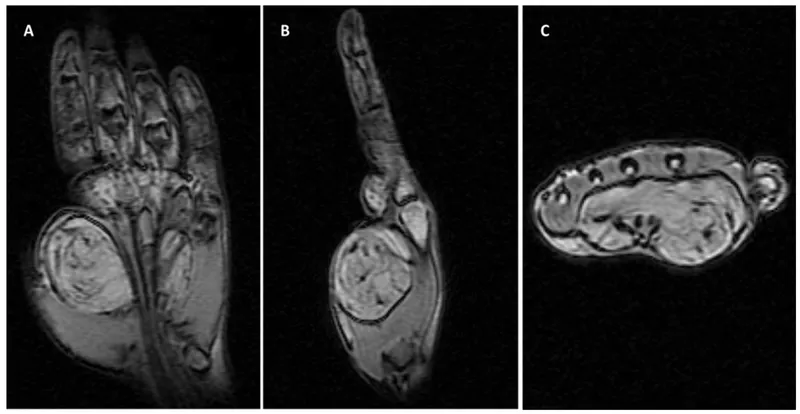

| GCTTS | Synovium | Firm, lobulated, painless mass; hemosiderin-laden macrophages | Fingers, hand, wrist | Marginal excision |

⭐ MRI is the imaging modality of choice for local staging and characterization of soft tissue tumors, detailing extent and neurovascular relations.